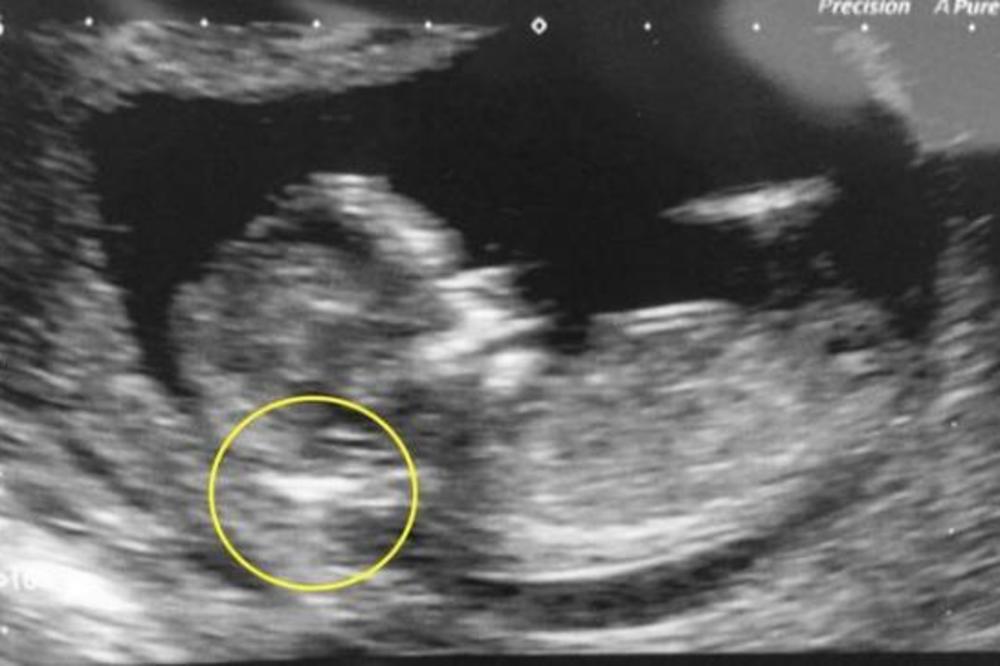

U telu malene Icamare rasla je njena sestra bliznakinja, a lekar je to uočio tokom ultrazvuka, dok je devojčica još bila u stomaku svoje majke Monike Vege (33).

Opstetričar, koji je Moniku poslao kod dr. Migela Para-Savedra, mislio je da nerođena beba ima nekakvu cistu, ali prevario se. Bilo je to sićušno, napola razvijeno telo bez srca i mozga u bebinom abdomenu, nešto što se događa vrlo retko, otprilike u jednom naspram pola milionaa rođenja. Majku Moniku je dr. Para-Savedra prvi put video kada je bila u 35. nedelji trudnoće.

Odmah ju je pregledao kolor doplerom i 3D/4D ultrazvučnim snimanjem. Ono što je video šokiralo ga je. U bebi je video prostor ispunjen tečnošću u kojoj je bilo minijaturno dete. Ono se zasebnom pupčanom vrpcom opskrbljivalo krvlju, a pupčana vrpca završavala je na crevu većeg blizanca, tj, malene Icamare.